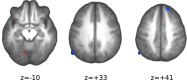

Mental effort is a common phenomenological construct deeply linked to volition and self-control. While it is often assumed that the amount of exertion invested in a task can be voluntarily regulated, the neural bases of such faculty and its behavioural effects are yet insufficiently understood. In this study, we investigated how the instructions to execute a demanding cognitive task either "with maximum exertion" or "as relaxed as possible" affected performance and brain activity. The maximum exertion condition, compared to relaxed execution, was associated with speeded motor responses without an accuracy trade-off, and an amplification of both task-related activations in dorsal frontoparietal and cerebellar regions, and task-related deactivations in default mode network (DMN) areas. Furthermore, the visual cue to engage maximum effort triggered an anticipatory widespread increase of activity in attentional, sensory and executive regions, with its peak in the brain stem reticular activating system. Across individuals, this surge of activity in the brain stem, but also in medial wall cortical regions projecting to the adrenal medulla, positively correlated with increases in heart rate, suggesting that the intention to willfully modulate invested effort involves mechanisms related to catecholaminergic transmission and a suppression of DMN activity in favor of externally-directed attentional processes.